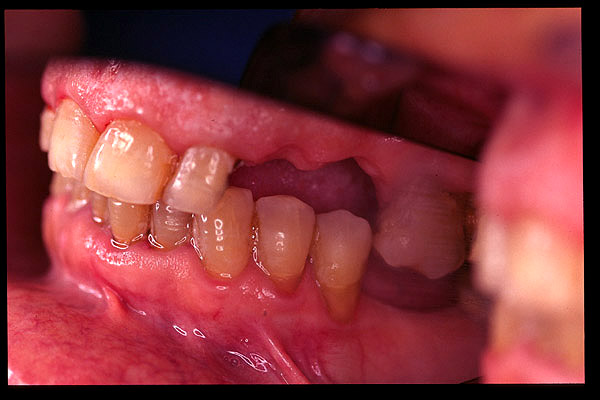

CM Falta de contactos interoclusales

CM Extrusión de incisivos inferiores por falta de contactos oclusales